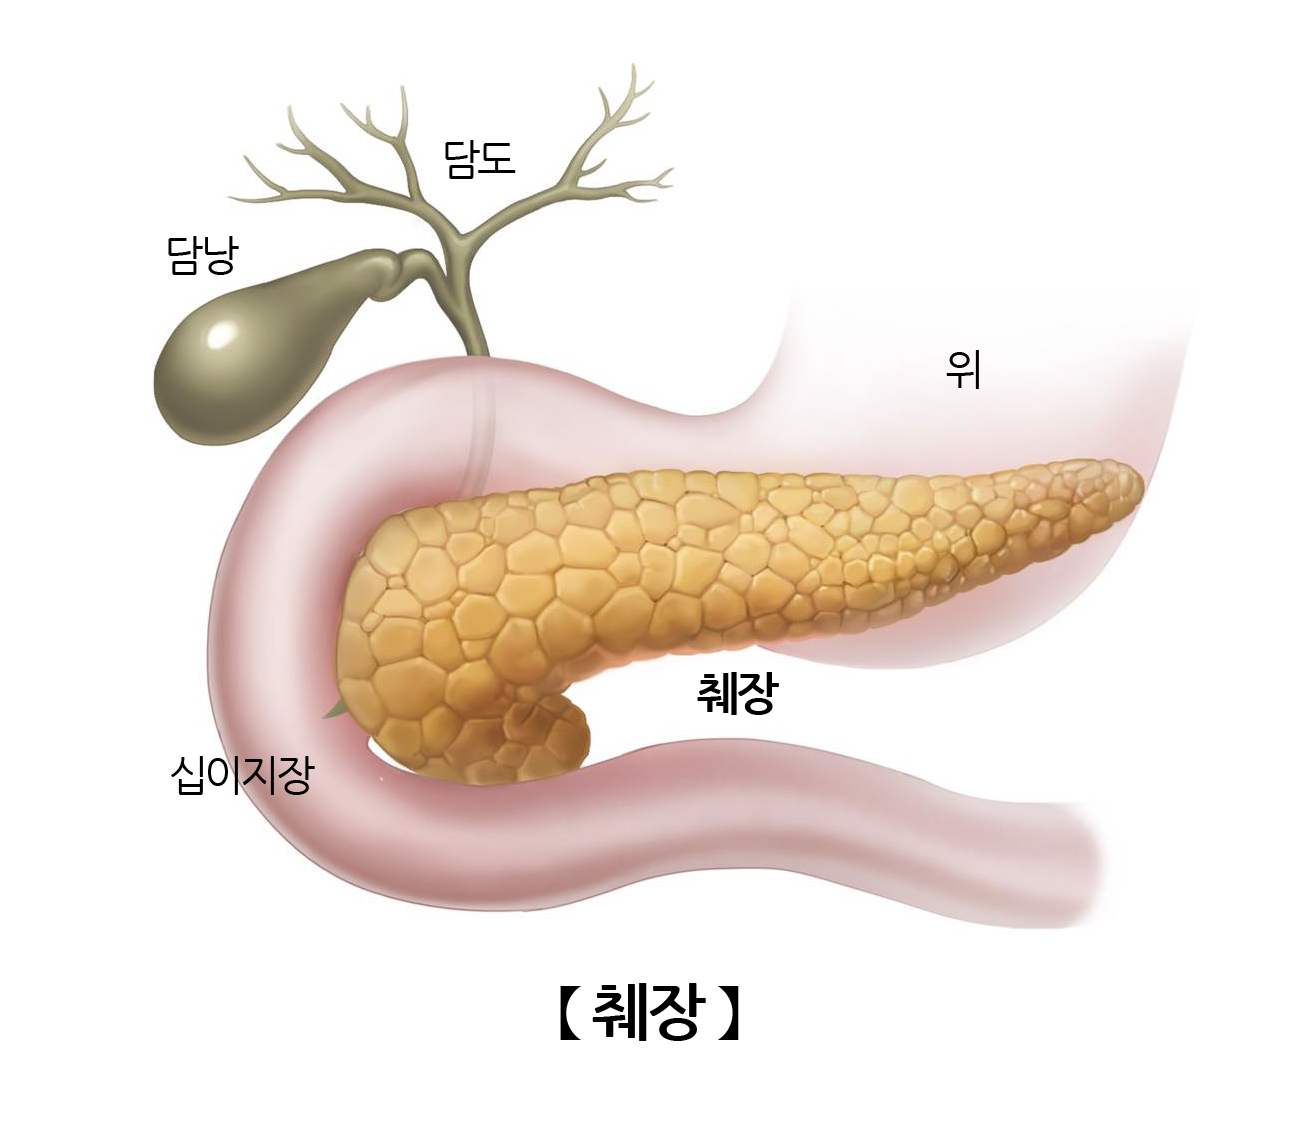

위장의 뒤쪽에 위치한 후복막 장기로 소화기관 중 하나입니다. 췌장은 소화효소를 분비해 음식물을 소화시키는 기능과 우리 몸의 혈당을 조절하는 인슐린과 글루카곤 호르몬을 분비하는 기능을 수행합니다.

위치췌장의 앞으로는 횡행결장과 위가, 아래쪽으로는 소장과 인접해있습니다. 췌장의 머리부위에는 하대정맥과 복부대동맥과 인접하며 몸통은 상장간막동맥, 상장간막정맥과 인접하며 꼬리부위는 좌측신장과 비장과 인접해있습니다.

췌장은 약 15cm, 무게는 약 100g 정도로 가늘고 긴 모양이며 머리, 몸통, 꼬리의 3부분으로 나눌 수 있습니다.

췌장세포에서는 췌액을 만들어 췌관을 통해 십이지장으로 분비하는데, 췌관이 십이지장으로 연결된 부위를 바터팽대부라고 합니다. 여기서는 췌장액 뿐만 아니라 간에서 만들어진 담즙도 함께 배출되는 통로로 췌장에 문제가 발생하면 담즙 배출 또한 함께 장애가 생길 수 있어 황달이 동반될 수 있습니다.